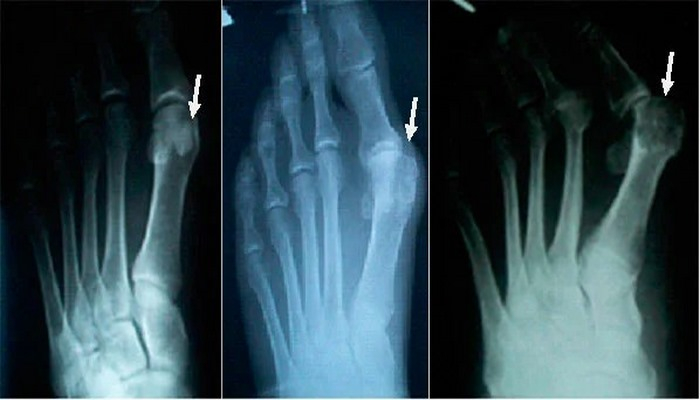

3. Поражение конкретных суставов

Типичный симптом, позволяющий узнать подагру, – поражение сустава большого пальца на ноге. Также часто при этом заболевании воспаление и боль локализуются в коленях, локтях, запястьях, пальцах рук.